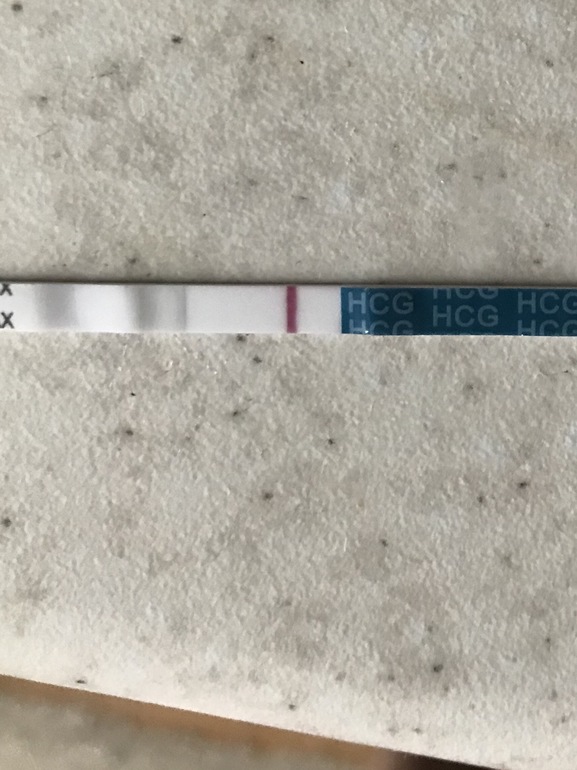

Вечером сделала Эвитест, появилась слабая полоска через минуту где-то, а после высыхания она пропала и тест остался отрицательный. И как это можно понять? Или это реагент такой на эвике?  Надеюсь ее будет видно, это мокрый.

Надеюсь ее будет видно, это мокрый.

И вот затемнила его, так лучше видно будет надеюсь.

Я вижу розовенькую полосочку

У меня такие всегда говорили о б.

Да, мне видно. Было и пропадала

Что-то там явно виднеется